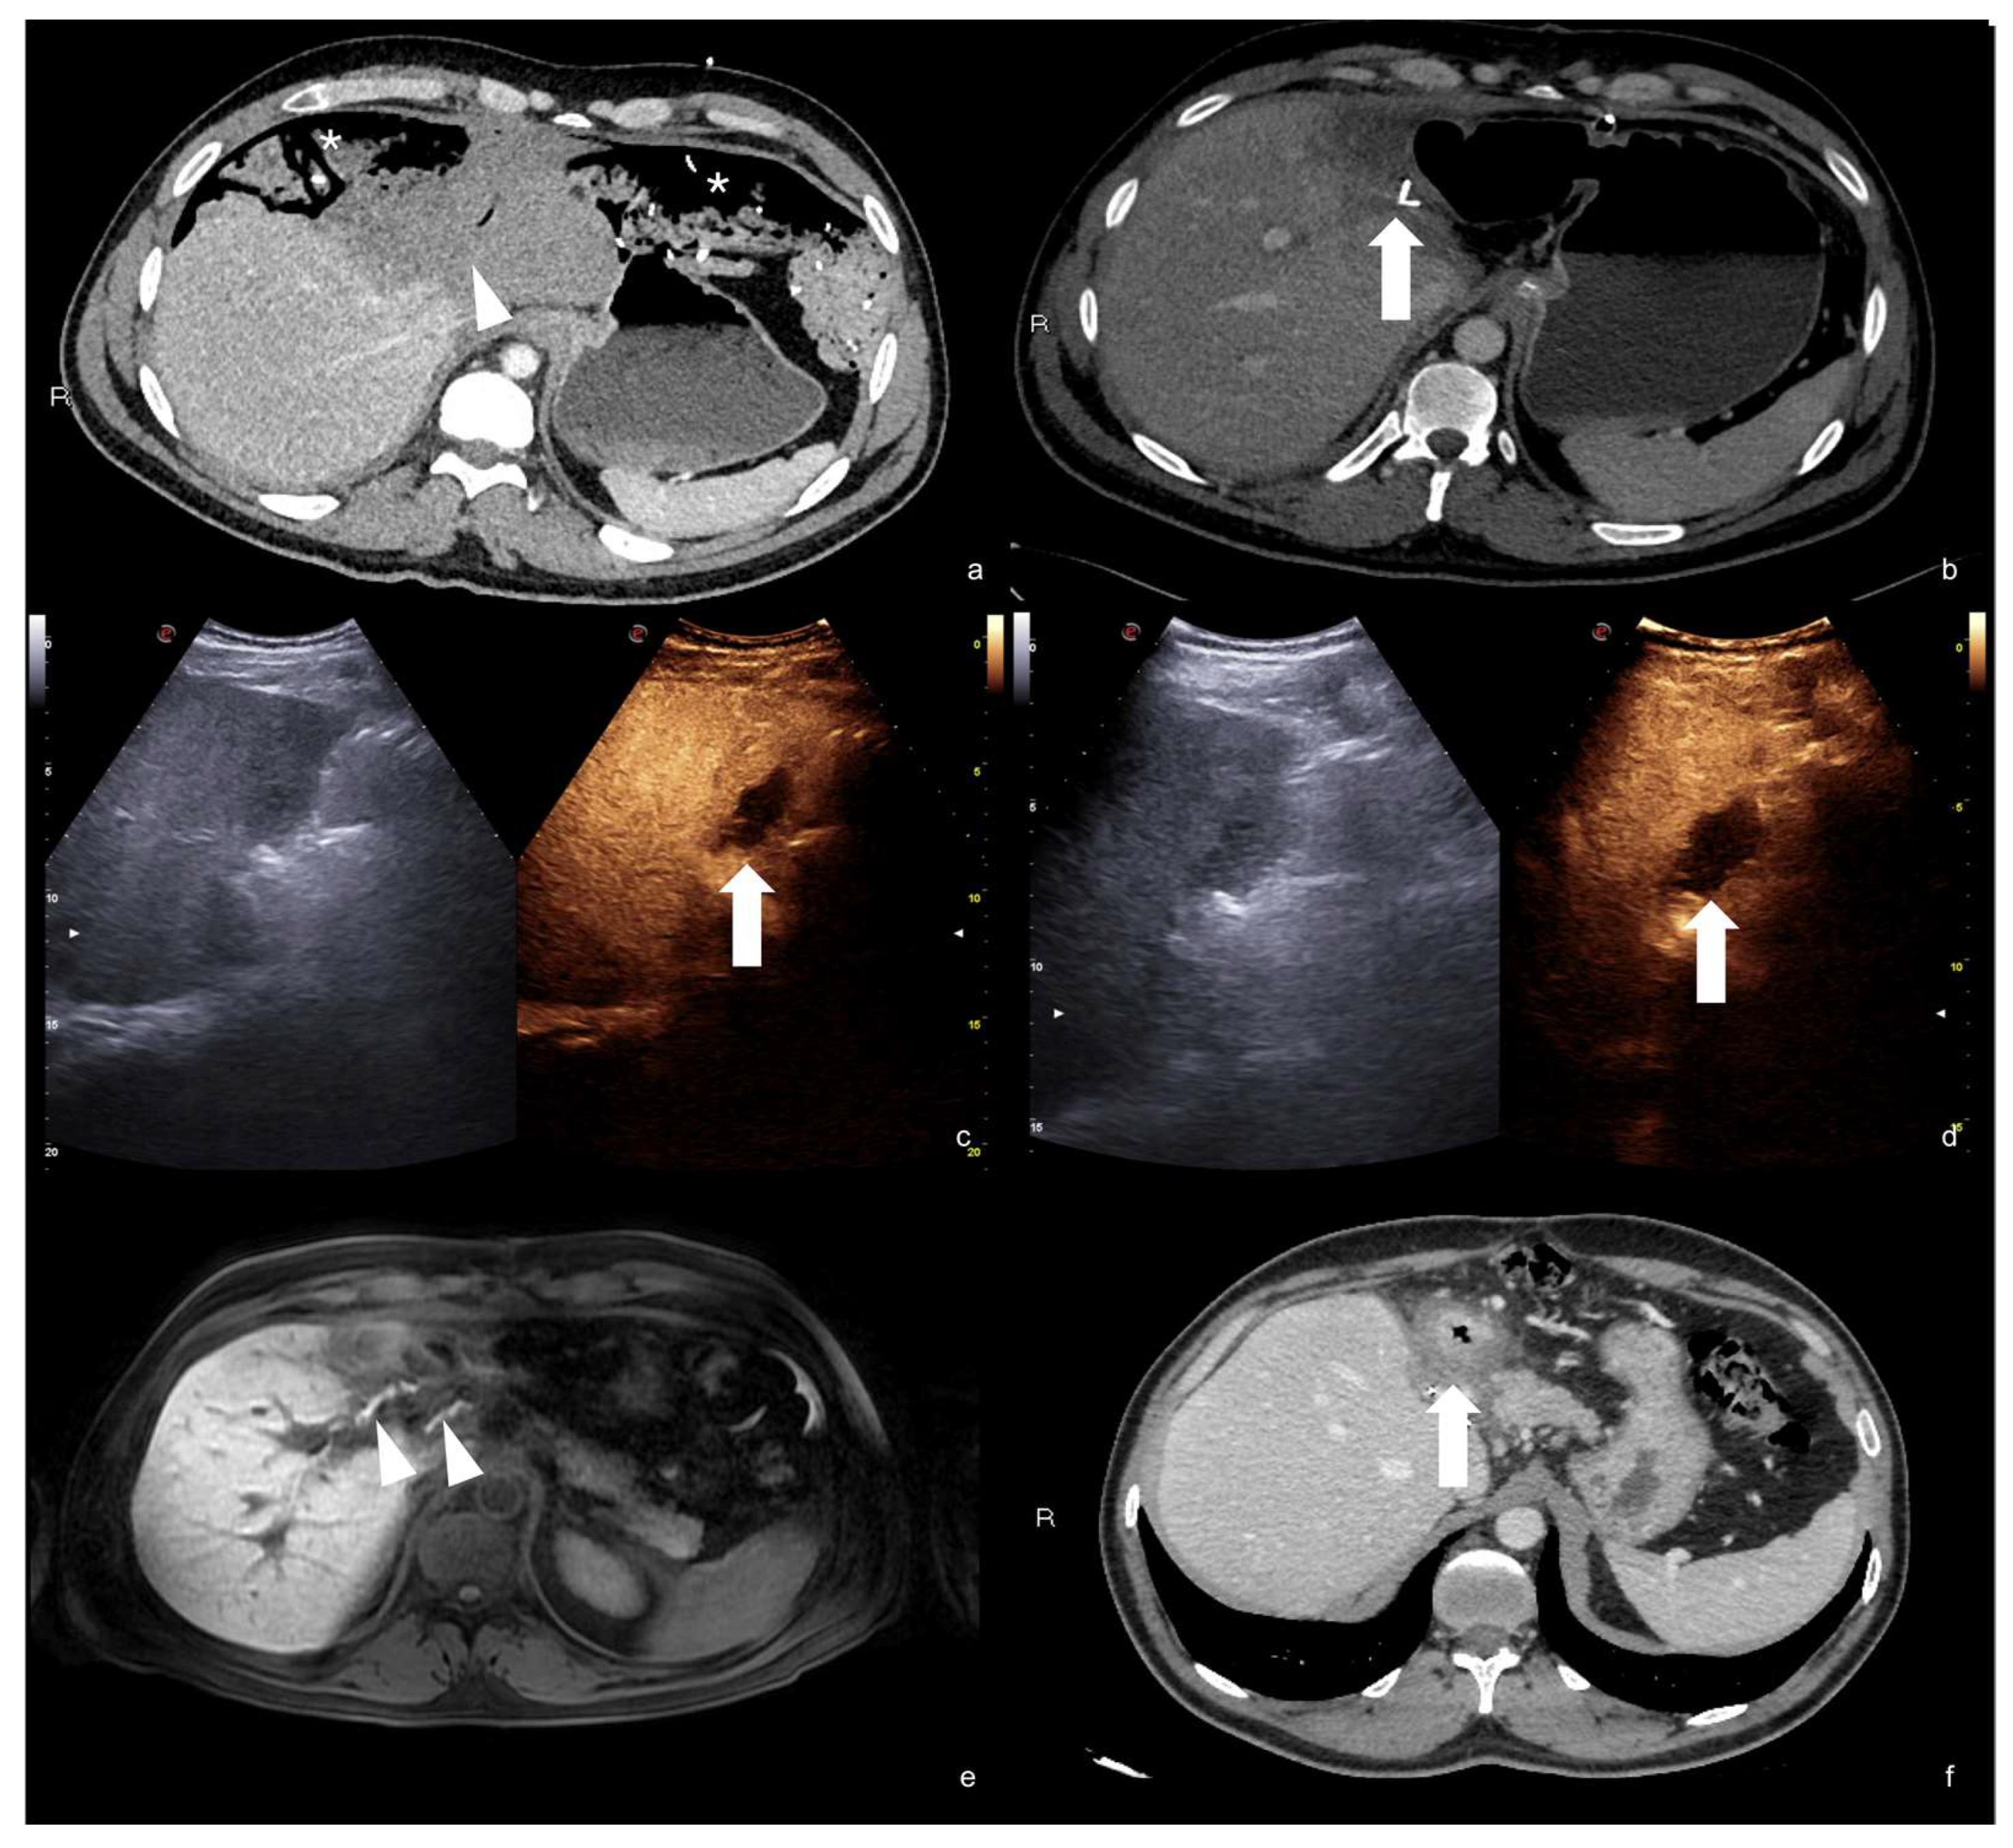

2.3.1. Solid Organ Injuries May Involve the Parenchyma and the Vessel

- Parenchymal injuries:

2.3.2. Vascular Injuries

- Active bleeding:

- Contained vascular injuries:

4. Case Series: Step-by-Step Practical Applications, Tips and Tricks during CEUS Follow-Up of Conservatively Managed Abdominal Trauma

4.1. Step 1

4.2. Step 2

4.3. Step 3

4.4. Step 4

4.5. Step 5